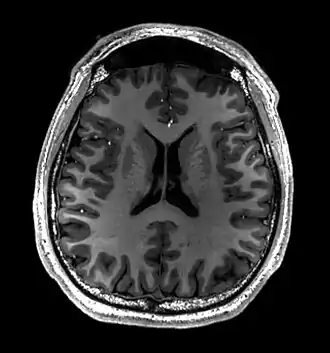

Cross-sectional T1-weighted MRI of a healthy human brain acquired with an ultra high-field MR of 7 Tesla field strength

This axial T2-weighted (CSF white) MR scan shows a normal brain at the level of the lateral ventricles.